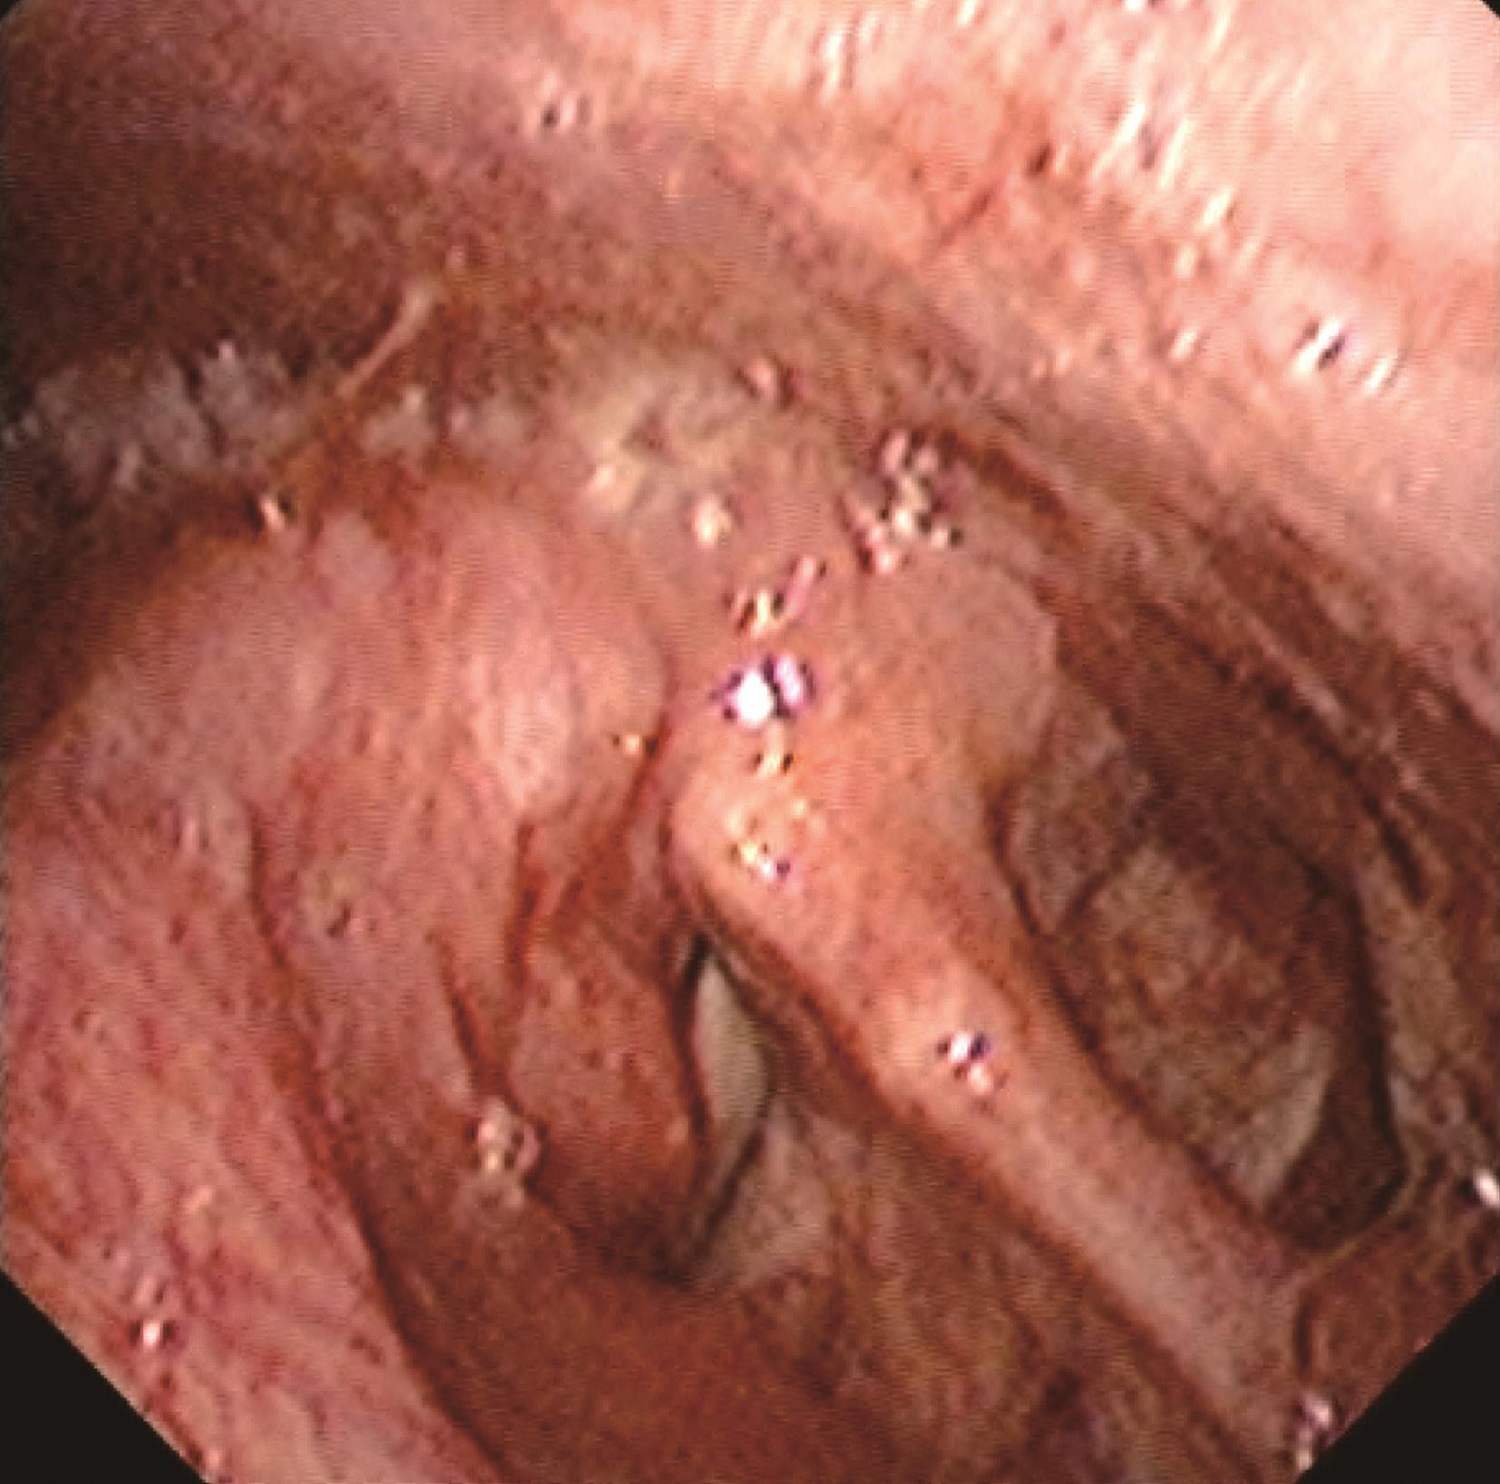

1.2014年1月10日电子喉镜检查

鼻咽部黏膜光滑,未见明显异常。口咽双侧扁桃体无肿大。舌根部淋巴滤泡略增生。右侧梨状窝内侧壁灰白粗糙新生物,形态不规则,累及右侧梨状窝外侧壁、会厌右侧缘和右侧杓会厌皱襞,右侧披裂黏膜及右侧室带肿胀,右侧声带固定,左侧声带活动正常,杓间区及环后区黏膜光滑(图1~图3)。

图2肿物累及右侧梨状窝外侧壁、会厌右侧缘和右侧杓会厌皱襞